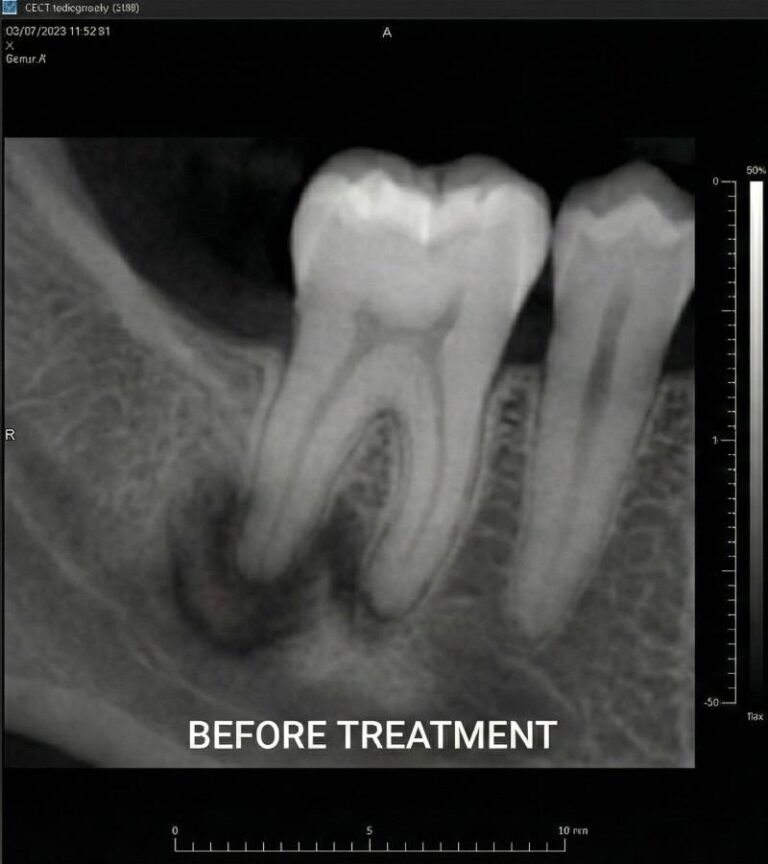

Endodontics focuses on treating infection and inflammation inside the tooth to relieve pain and preserve the natural structure. When decay, trauma or infection reach the dental pulp, endodontic treatment—commonly known as root canal therapy—is used to remove infected tissue, clean and disinfect the canals, and seal the tooth to prevent reinfection.

Our endodontic dentists use rotary instruments, digital imaging and microscope-assisted techniques to deliver precise, comfortable care. We also provide retreatment and apicoectomy for complex cases where a previous root canal has failed. By preserving your natural tooth whenever possible, endodontic care often provides a more stable long-term solution than extraction and replacement. Endodontic care includes root canal therapy to treat active infection and retreatment when a previous root canal needs further care to preserve the tooth.

Our endodontic specialists use advanced microscopes and digital imaging to perform precise treatment. Unlike general dentistry, microscopic endodontics helps identify hidden canals and address complex infections while preserving as much natural tooth structure as possible.

When the pulp inside your tooth becomes inflamed or infected due to decay, trauma or cracks, the pain can be debilitating. Left untreated, infection can spread to the jawbone and surrounding tissues and lead to more serious complications. Root canal therapy removes the source of infection, preserves your tooth and prevents further damage to neighbouring teeth.